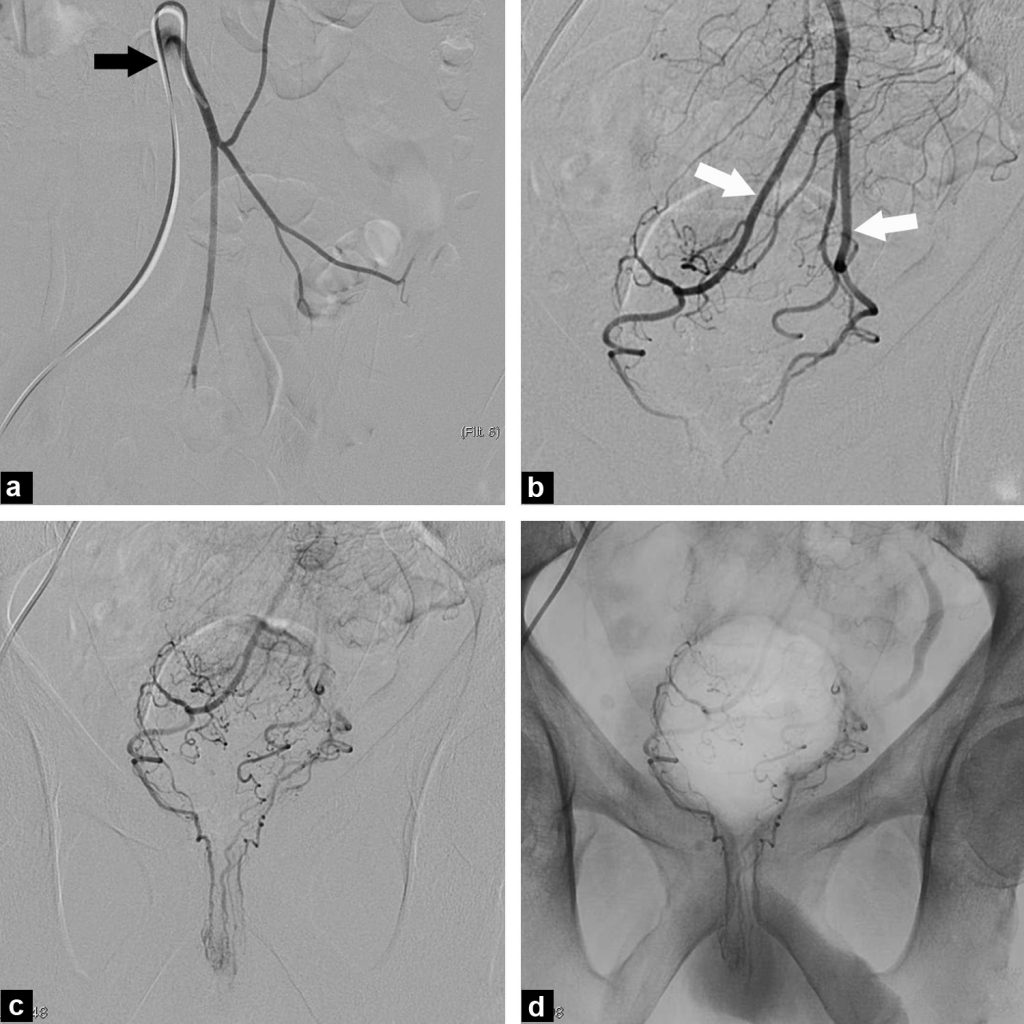

(PDF) New Technique of Embolization of the Hemorrhoidal Arteries Using Hemorrhoid Embolization Interventional Radiology Web recently, endovascular embolization of hemorrhoids has emerged. Web endovascular coil or particle embolization of the superior rectal arteries, known as emborrhoid technique, is a minimally. Web embolization of the rectal arteries (ie, emborrhoid) has recently emerged as an effective treatment option,. Web outcomes of hemorrhoidal artery embolization from a multidisciplinary outpatient interventional center. Web endovascular coil or particle embolization. Hemorrhoid Embolization Interventional Radiology.

Anatomy and General Technique of Hemorrhoidal Embolization Hemorrhoid Embolization Interventional Radiology Web outcomes of hemorrhoidal artery embolization from a multidisciplinary outpatient interventional center. Web embolization of hemorrhoids through minimally invasive technique is a technically feasible, safe, and effective treatment. Web endovascular coil or particle embolization of the superior rectal arteries, known as emborrhoid technique, is a minimally. Clusters of tiny veins lie just beneath the mucous membranes that line. Web embolization. Hemorrhoid Embolization Interventional Radiology.

Embolization of the Superior Rectal Arteries for Hemorrhoidal Disease Hemorrhoid Embolization Interventional Radiology Web embolization of hemorrhoids through minimally invasive technique is a technically feasible, safe, and effective treatment. Web embolization of the rectal arteries (ie, emborrhoid) has recently emerged as an effective treatment option,. Web endovascular coil or particle embolization of the superior rectal arteries, known as emborrhoid technique, is a minimally. Web outcomes of hemorrhoidal artery embolization from a multidisciplinary outpatient. Hemorrhoid Embolization Interventional Radiology.